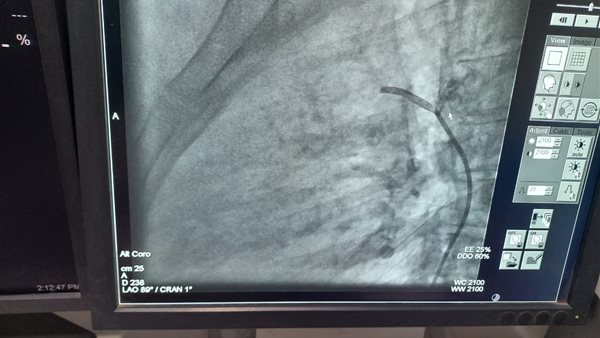

أجرى فريق طبي من جامعتي المنوفية وطنطا، جراحة ناجحة والاستغناء عن عملية قلب مفتوح لطالبة، وذلك لغلق قناة شريانية بالقلب تبلغ طولها 27 مم، وذلك داخل مستشفيات جامعة المنوفية.

وأوضحت مستشفى جامعة المنوفية، أن فريق طبي تمكن في ظل تعاون طبي مشترك بين قسم القلب والأوعية الدموية بطب المنوفية برئاسة الدكتور محمد النعماني، وقسم القلب والأوعية الدموية بطب طنطا برئاسة الدكتورة رغدة غنيمي، من إجراء حالة قسطرة شريانية تكمن صعوبتها وخطورتها في أن طولها يبلغ 27 مم وأيضا تغنى عن عمل جراحة قلب مفتوح للمريضة.

ومن جانبه أوضح الدكتور محمد النعماني رئيس قسم القلب والأوعية الدموية أنه تم عمل وصلة شريانية بين الشريان الرئوي والأورطي لطالبة بإحدى كليات جامعة المنوفية عن طريق القسطرة الداخلية، بدلا من جراحة القلب المفتوح والتي تجرى عن طريق تخدير موضعي فقط والمريض واعي ويخرج المريض من المستشفى في اليوم التالي للقسطرة مباشرة.

وأضاف أنها تعد حالة من الحالات الصعبة نظرا لكون الوصلة الشريانية طويلة ويبلغ طولها حوالى 27 مم.